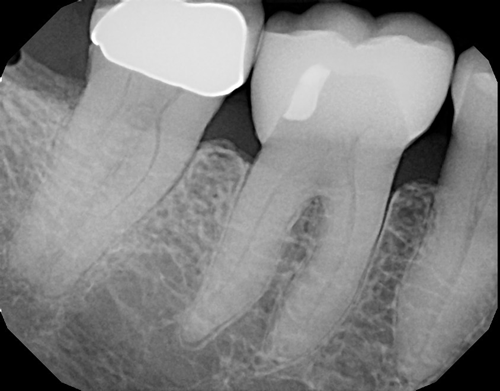

The crown and printed model were returned to my office. At the seating appointment, the provisional crown was removed and the final crown was tried in. Contacts, margins and occlusion were evaluated and no adjustments were needed. The crown was bonded to place using a self-adhesive resin cement (Fusion-ZR Dual Cure Resin Cement, Taub Products). It can be seen in place from the facial view in Figure 11 and the occlusal view in Figure 12. The radiograph in Figure 13 shows the excellent fit of the digitally fabricated crown.

Fig. 11 Fig. 12 Fig. 13